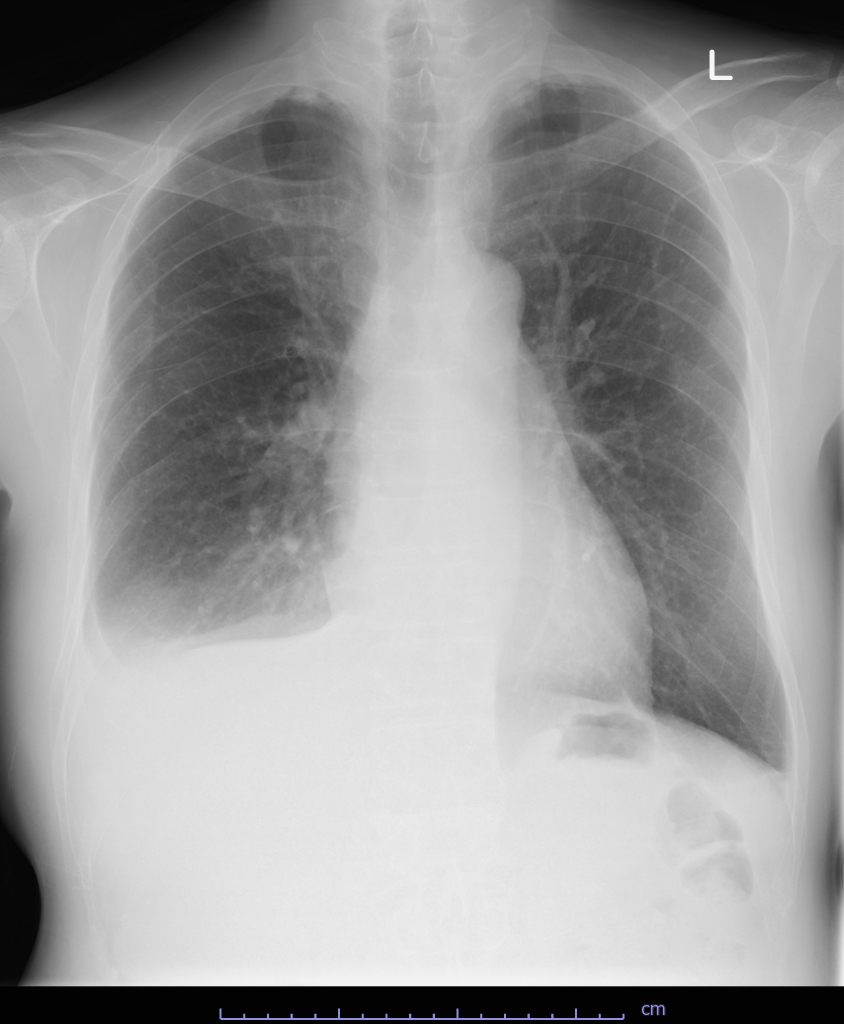

A 59-year-old man presented with bilateral lower leg edema. His past medical history was no history of open-heart surgery, chest radiation, or preceding febrile illness. His height was 176cm, body weight was 82.1kg. His vital signs were as follows: blood pressure 98/68 mmHg, heart rate 82 bpm, and oxygen saturation 97% on room air. Chest X ray showed bilateral pleural effusion. (Fig 1)